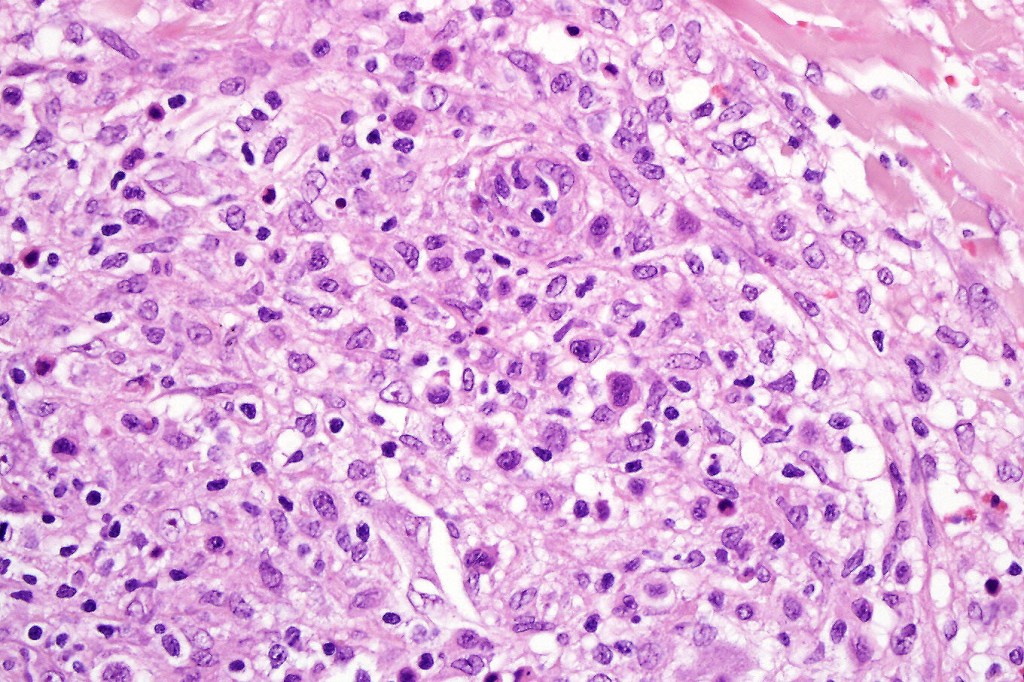

•Type C: 7-10% nodular infiltrate similar to primary cutaneous anaplastic large cell lymphoma